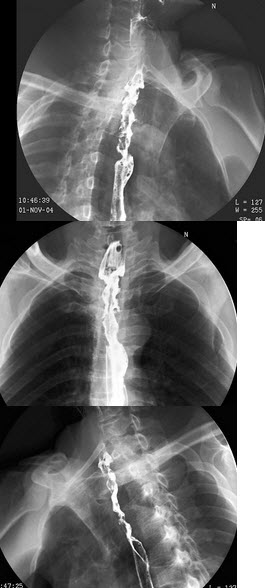

11、单项选择题

男,11岁。自出生后出现活动后憋喘、口唇发紫。检查如图所示。最可能的诊断是()

A.完全性肺静脉异位引流-心下型

B.完全性肺静脉异位引流-心上型

C.完全性肺静脉异位引流-心内型

D.完全性肺静脉异位引流-混合型

E.法洛四联症